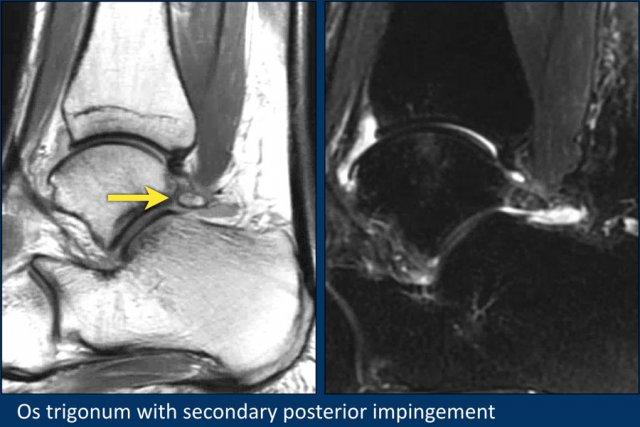

Os Trigonum

Ở bàn chân và cổ chân, có thể thấy nhiều xương phụ (accessory ossicles) khác nhau.

Xương phụ phổ biến nhất là os trigonum, là một mấu xương (apophysis) nổi bật chưa hợp nhất của củ bên (lateral tubercle) xương sên.

Os trigonum hiện diện trong dân số bình thường với tỷ lệ khoảng 5-15%.

Sự chèn ép os trigonum và các mô mềm xung quanh giữa xương chày và xương gót trong động tác gấp lòng bàn chân (plantar flexion) có thể là nguyên nhân gây hội chứng chèn ép phía sau (posterior impingement).

Điều này đặc biệt hay gặp ở các vũ công ballet.

Thuật ngữ “mỏm Stieda” (Stieda process) được dùng khi củ bên xương sên rất nổi bật.

Điều này cũng có thể dẫn đến hội chứng chèn ép phía sau.

Đây là một bệnh nhân khác có os trigonum.

Trên các chuỗi xung fatsat, có phù nề ở os trigonum và các mô mềm xung quanh.

Đây là một ví dụ về hội chứng chèn ép phía sau do os trigonum có triệu chứng.